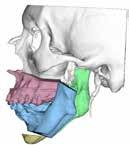

Para completar el estudio, se solicitó una tomografía axial computoriza da craneofacial (TAC) (Figura 1), dónde tras un examen exhaustivo a través de distintos cortes y reconstrucción 3D, evidenciamos una anquilosis de la ATM a la base de cráneo, desapareciendo por completo la anatomía nor mal de la ATM y su relación habitual con las distintas estructuras neurovas culares, así como la gran deformidad esquelética resultante del crecimiento y desarrollo craneofacial anormal.

Una vez los dientes fueron colocados mediante ortodoncia en el lugar estratégico en la arcada, se realizó una planificación quirúrgica 3D de los movimientos quirúrgicos de los maxilares en colaboración con la empresa americana encargada de la confección de la prótesis. Se diseñaron así unas guías quirúrgicas para la resección del bloque anquilótico, unas guías qui rúrgicas para la realización de la mentoplastia y el diseño de la prótesis individualizada y personalizada (Figura 2).

Gracias a esta planificación, se logró una mayor precisión en los movi mientos quirúrgicos, una mayor predictibilidad y reproducción, una dismi nución de los riesgos quirúrgicos por mediciones de estructuras anatómicas concretas (como la arteria carótida interna, el nervio facial, el nervio man dibular, la arteria maxilar interna…) (Figura 1) y un menor tiempo operato rio, entre otras ventajas.

Tras la planificación, se imprimió el esqueleto craneofacial en forma de modelo esterolitográfico en 3D (Figura 2A), para de manera intraoperato ria poder corroborar la localización quirúrgica, al ser una cirugía con una enorme dificultad de orientación tridimensional (Figura 2B).

Figura 1. Diagnóstico prequirúrgico del bloque anquilótico. Imágenes TAC en 3D, corte axial y corte sagital..

Figura 2.

Planificación quirúrgica 3D.

A) Diseño 3D de los movimientos quirúrgicos y de las osteotomías maxilares, mandibulares y de mentón.

B) Diseño 3D de las guías de corte para la resección del bloque anquilótico e impresión 3D de modelo estereolitográfico para uso intraquirúrgico.

C) Diseño 3D prótesis customizada, con segmento condíleo y segmentos de fosa glenoidea, y de los tornillos.